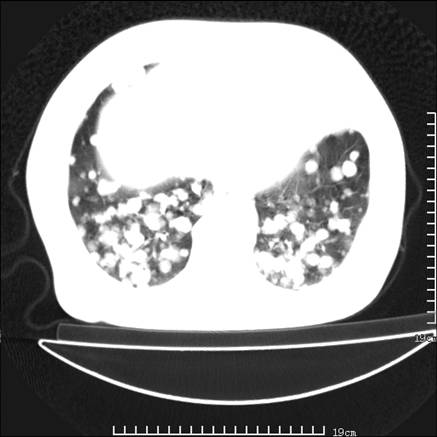

张男,75岁,干咳半年余,小便不利二年,b超检查前列腺增大,未见明显肿块;前列腺癌血生化检查多项指标明显增高。

双肺内多发转移瘤,纵膈淋巴结转移。来源前列腺?建议盆腔mri进一步检查。

双肺转移满了。

两肺广泛转移瘤。